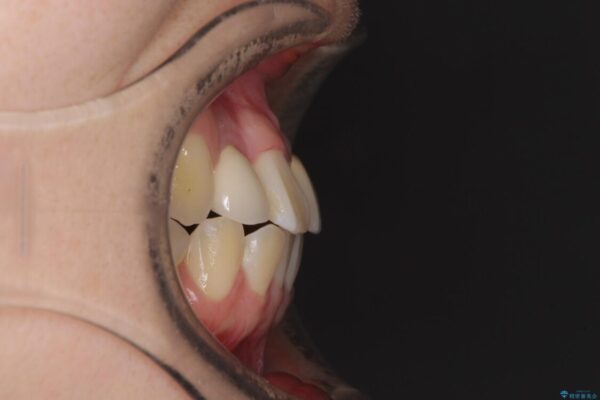

治療前

• 虫歯治療ついでに歯並びの後戻りを改善 インビザラインによる矯正治療 治療前画像